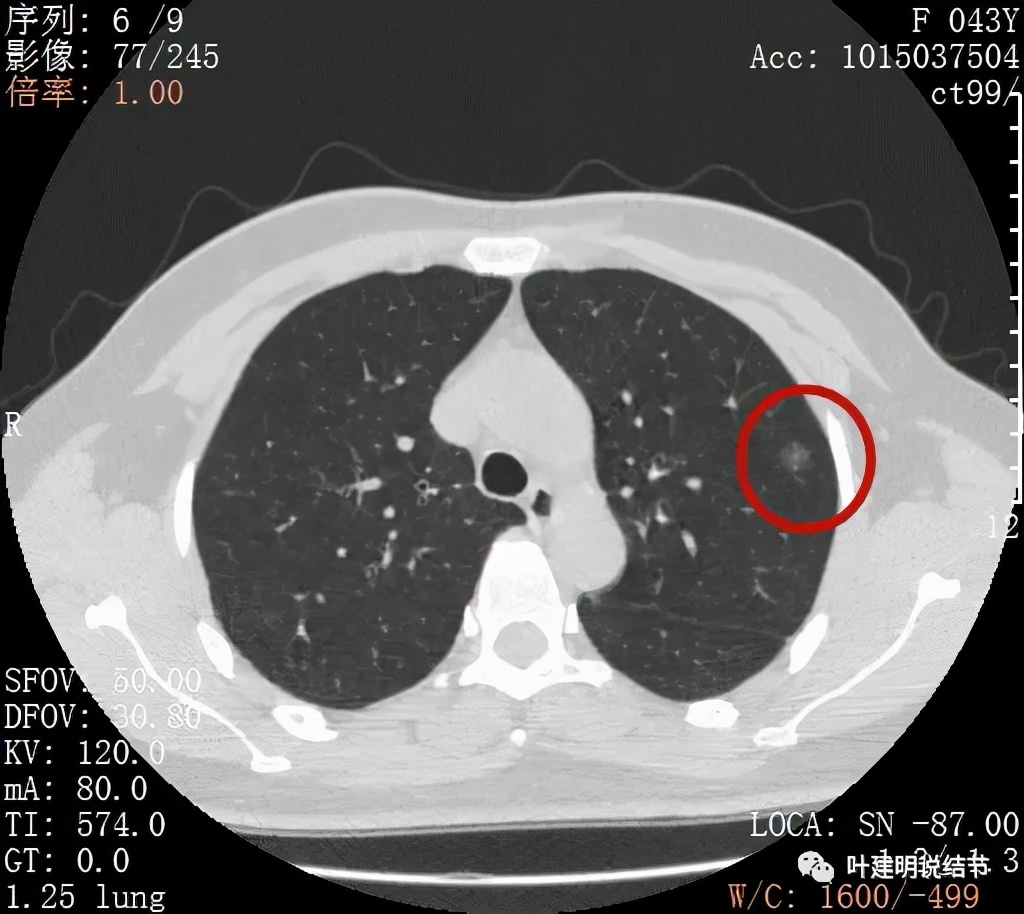

金华的某A,女性,今年43岁,检查发现左肺上叶结节2月余。其于当时说是在外院检查发现,到我门诊找我看过的(我是记不清楚了),大概是告诉她:考虑早期肺癌可能性大,但密度还低,边缘显模糊。让她再随访观察下再决定手术与否。这次送孩子上大学后,她马上来医院全面检查并若需要手术就决定手术了的。我们先来看她的平扫片子:

可见左肺上叶磨玻璃结节,边缘略显模糊,瘤肺边界不是很清,但总体上看,病灶轮廓仍是较为清楚的,而且有所层面有微小血管进入,病灶密度也不均匀,感觉有点杂乱。这种病灶如果随访了2个多月仍持续存在,也没多少变化的话,基本上要考虑肿瘤范畴的结节。为了看细节,我们建议其再查了靶扫描,图像如下: